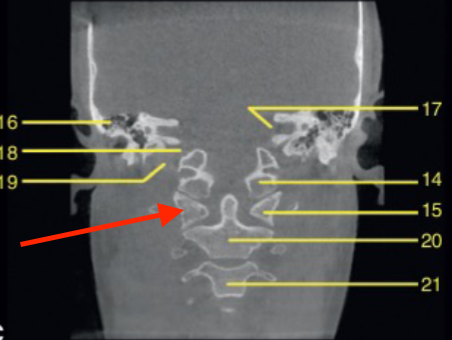

coronal

what plane

posterior of maxillary sinus

where is this slice

mandibular canal/inferior alveolar canal

what is the ARROW pointing to